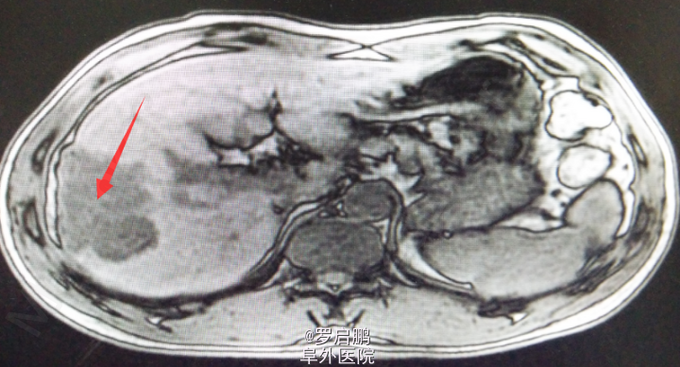

患者 男 48岁 主诉:发现肝脏占位半月 现病史:半月前患者因慢性乙型肝炎复查腹部超声发现右肝占位 既往:慢性乙肝20年,未规律治疗。 个人史:吸烟史25年20支/天,饮酒史13年,白酒2两/次。

超声:右肝高回声光团,胆囊、肝内外胆管、脾脏、双肾未见异常 腹部MRI:肝右叶占位 腹部平扫+增强:肝右叶占位,肝内多发小密度,左肾囊肿,腹膜后淋巴结肿大

肝右叶占位,肝癌? 前入路右半肝切除,LC 鉴别诊断:原发性肝癌;肝转移癌;肝海绵状血管瘤;肝腺瘤;血管平滑肌脂肪瘤。

注意术中循环维持,备血、血浆。术中平稳。术中病理:(右半肝)低分化胆管腺癌,可见坏死,肝内可见多发卫星灶,紧邻肝被膜,切缘未见特殊。术后恢复良好出院。